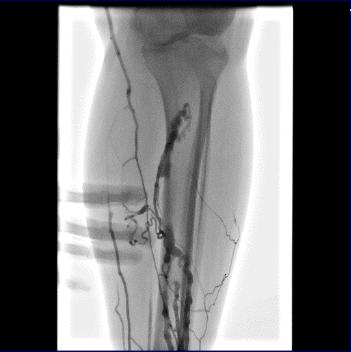

急诊造影:小腿深静脉通畅,腘静脉通畅,见图2

图2